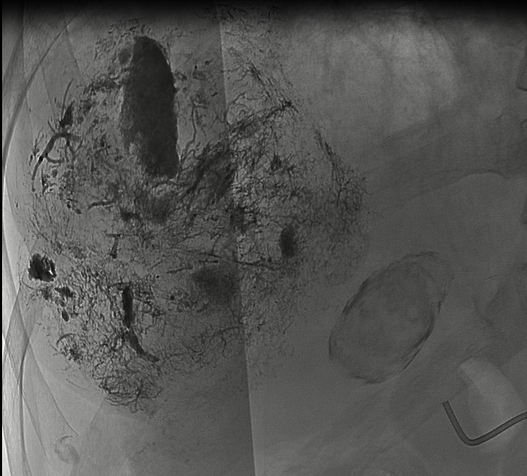

治療后造影